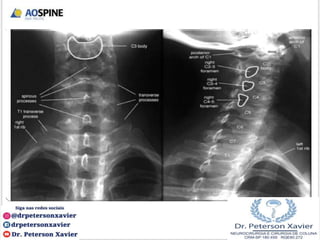

Região cervical (CI – CVII)

Os processos espinhosos de C1-6 freqüentemente são bífidos;

Todas as vértebras cervicais possuem três forames: um forame

vertebral e dois forames transversários

ANATOMIA SUBAXIAL

CIII - CVI

CVII